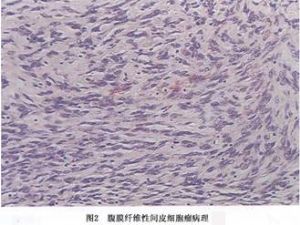

(1)纤维性间皮瘤:纤维性间皮瘤瘤细胞由梭形细胞组成,细胞呈长梭形,伴有多少不等的胶原纤维,这种类型多见于局限性间皮瘤。在纤维性间皮瘤有时很难与纤维组织肿瘤相区别,瘤细胞呈梭形,细胞周围可有胶原化,甚至可有编织状结构,局灶性钙化或骨化,当间质有明显的纤维化或玻璃样变时,有人称它为韧带样间皮瘤。最近亦有人将来自间皮下的结缔组织来源的肿瘤称为腹膜纤维瘤。来自表层间皮细胞的才称纤维性间皮瘤。但单纯根据组织形态,有时难以将两者区别开来(图2)。

(1)纤维性间皮瘤:纤维性间皮瘤瘤细胞由梭形细胞组成,细胞呈长梭形,伴有多少不等的胶原纤维,这种类型多见于局限性间皮瘤。在纤维性间皮瘤有时很难与纤维组织肿瘤相区别,瘤细胞呈梭形,细胞周围可有胶原化,甚至可有编织状结构,局灶性钙化或骨化,当间质有明显的纤维化或玻璃样变时,有人称它为韧带样间皮瘤。最近亦有人将来自间皮下的结缔组织来源的肿瘤称为腹膜纤维瘤。来自表层间皮细胞的才称纤维性间皮瘤。但单纯根据组织形态,有时难以将两者区别开来(图2)。